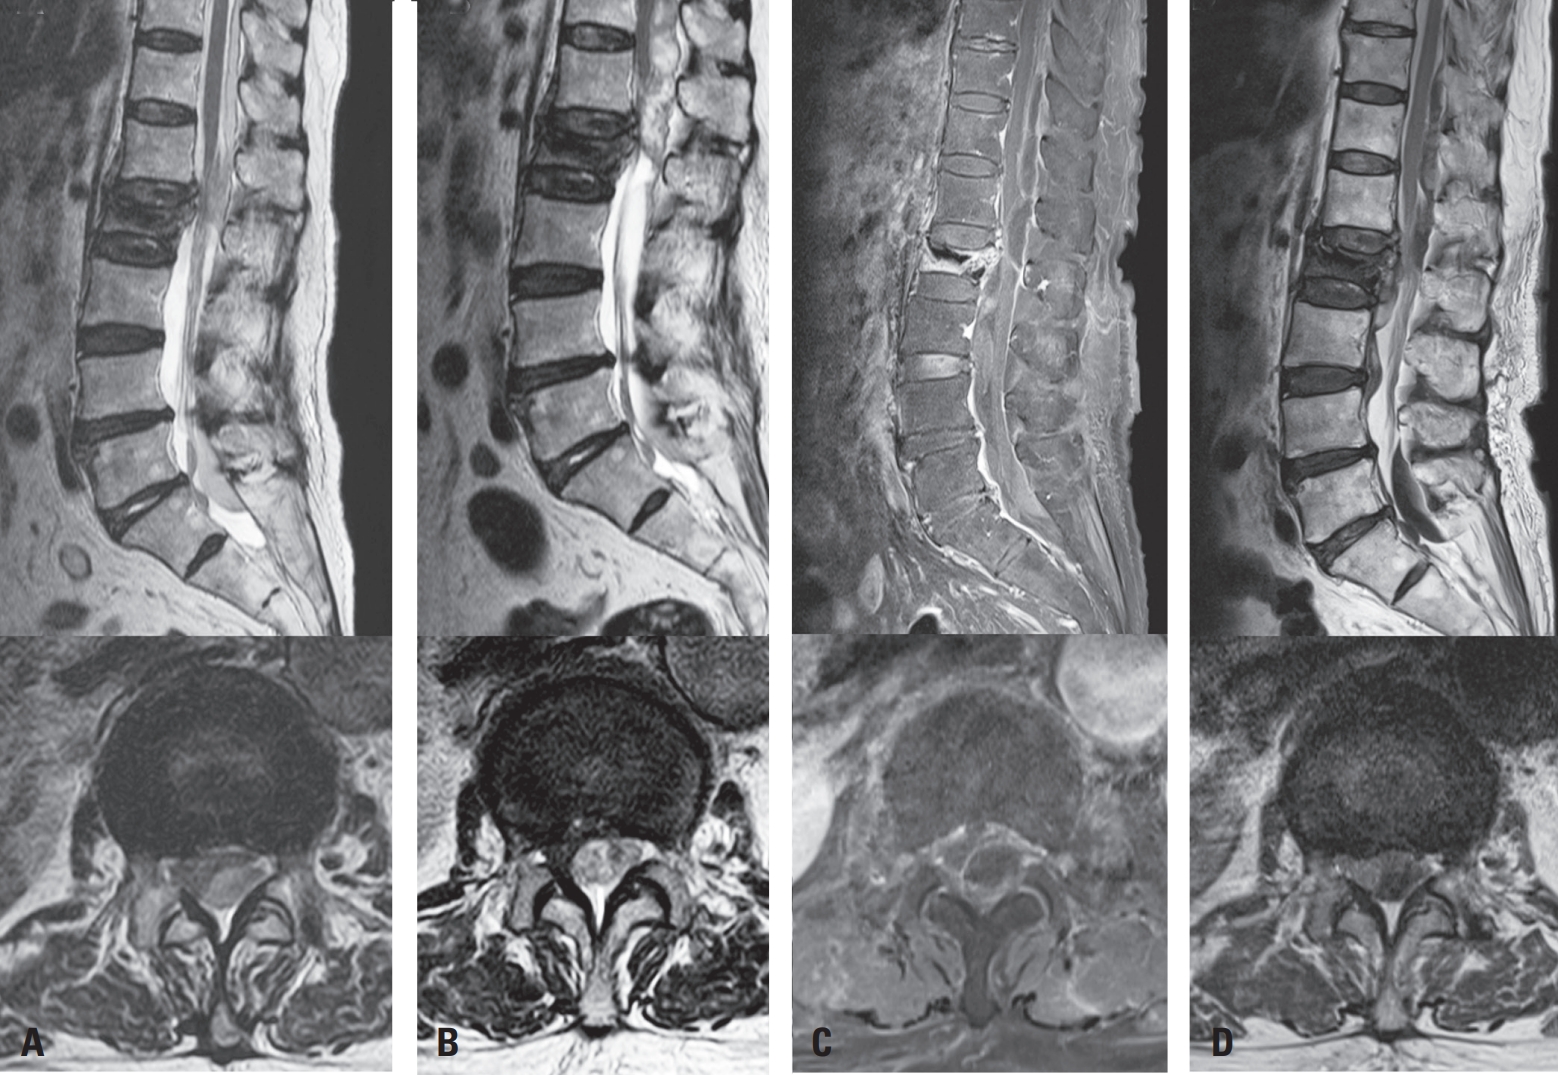

Routine MRI on POD 1 revealed a subdural hematoma at L1–2 and L5–S1 (Fig. 2A), which progressed cranially to the thoracic spine by POD 2 (Fig. 2B). The patient developed new back and buttock pain but remained neurologically intact. Intravenous dexamethasone (4 mg every 6 hours) was administered per spinal cord compression protocol.9)

On POD 4, follow-up MRI showed no further cranial extension of the thoracic subdural hematoma but revealed a new subdural hematoma at the L3–4 level (Fig. 2C). As the patient remained neurologically stable without new symptoms, enoxaparin (50 mg twice daily) was resumed on POD 6, and corticosteroids were gradually tapered.

By POD 11, MRI demonstrated partial resolution of the hematoma with a mixed subdural and epidural appearance (Fig. 2D). Warfarin was reintroduced and gradually resumed at the original dose. The patient was discharged without neurological complications and remained symptom-free at one-month follow-up. This case was conducted in accordance with institutional ethical guidelines and approved by the Institutional Review Board of Eunpyeong St. Mary’s Hospital (IRB No. PC25ZISI0119).

Fig. 2.

Serial postoperative MRI showing the evolution of spinal subdural hematoma. (A) POD 1: Subdural hematomas at L1–2 and L5–S1 levels with thecal sac compression. (B) POD 2: Cranial extension into the thoracic spine with increased spinal cord compression. (C) POD 4: No further thoracic progression, but a new subdural hematoma developed at L3–4. (D) POD 11: Partial resolution of the hematoma with mixed subdural and epidural components.